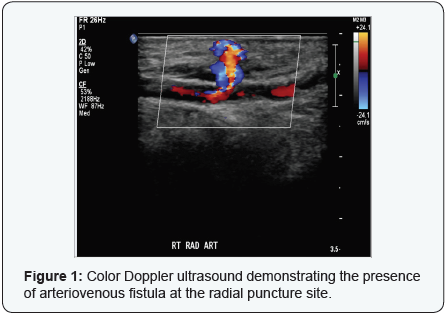

A 79-year-old male presented with chest pain and electrocardiographic evidence of inferior ST elevation myocardial infraction (STEMI). He underwent primary percutaneous coronary intervention via radial approach. Following the procedure he developed swelling at the access site and a bruit was heard. Ultrasonography demonstrated an arteriovenous fistula. He was managed conservatively and was seen few weeks later with complete resolution of his symptoms.

Transradial coronary angiography has significantly reduced access site complications. AVF is an abnormal connection between the arterial and venous systems. AVF is an extremely rare complication following the transradial approach and has been reported only in few cases [1-4]. On the other hand, AVF is a well-known complication of the transfemoral approach. The diagnosis is usually made by color Doppler ultrasonography.